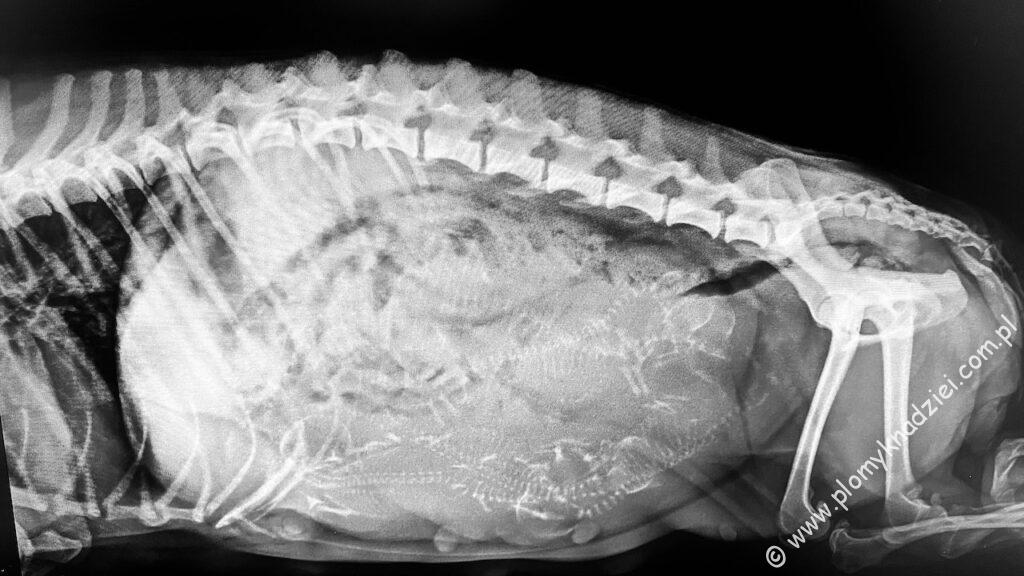

Oczekujemy na sześć maluszków! Kto ich się doliczy na zdjęciu? Pierwsza Ciąża Hope i takie wyzwanie! Suczki shih- tzu rodzą zazwyczaj od jednego do czterech szczeniąt. Przyszła mama jest pod stałą opieką weterynarza, jest karmiona w sposób adekwatny dla stopnia zaawansowania ciąży i odpowiednio suplementowana. Trzymamy kciuki za bezpieczny poród! Wszyscy mają być silni i zdrowi. Zarówno mama, jak i maleństwa.